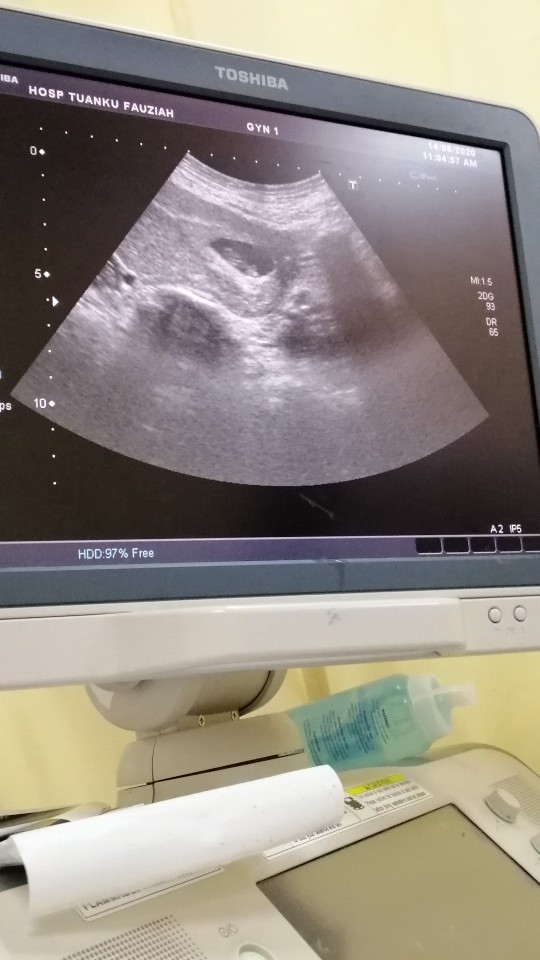

8weeks 4day

hye,so this morning i went to clinic for a scan. But doctor said she only see the sac. There is no baby. She suggested to wait for two weeks before i scan again. Is it normal? sorry for bad english

saya sekarang 8 week 4 day..hari jumaat saya ada scan doktor ckap xde heartbeat 😭😭..lg 2 mggu doktor suruh repeat scan..minta2 ada lg rezeki saya...risau + sedih 😢😢

Sy harini dah 8mgu 5hari. Alhamdulillah mgu lpas scan nmpak baby seketul. Tapi sy pernah baca sesetgah org masih tak nampak babynya lagi. Depends.

hi sis, sama sis saya pon scan hari 8w 1day then doc ckp nmpk sac je, so doc sruh dtng scan lgi 2 mnggu sama2 kite doa ye sis lpas dua mnggu dh nmpk beny and heartbeat